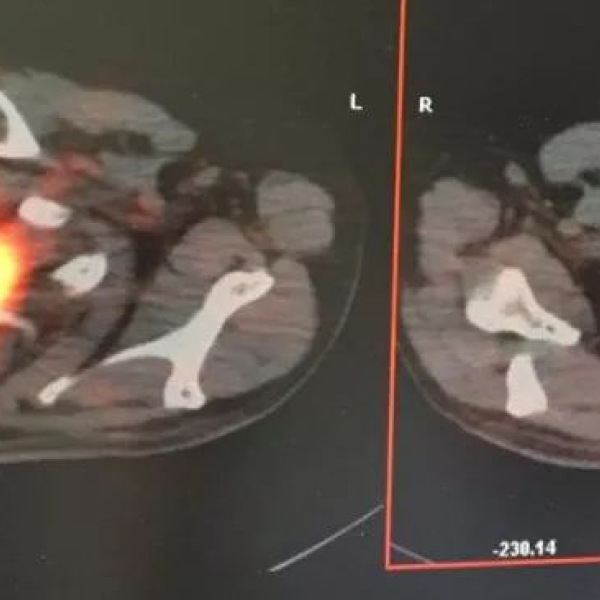

2016年11月01返院复查,行PET/CT示:左肺癌治疗后,与2016年06月15日PET/CT比较,左肺上叶原病灶处可见不规则软组织密度灶,相应PET层面示不均匀片状代谢增高灶,代谢活度较前降低,最大SUV3.4-(原最大SUV9.7);其相邻左肺下叶背段亦可见斑片状高密度灶,对应PET呈不均匀片状轻度异常高代谢,最大SUV3.0。检查结论:1.左肺癌治疗后纤维化;2.双肺炎症。其后患者定期复查*CT及腹部彩超未发现局部复发及远处转移征象,患者及家属对质子治疗疗效非常满意。现距质子治疗结束已近2年,我科每月对该患进行随访,该患工作、生活一切正常。

2016-06-15质子治疗前PET/CT 2016-11-01质子治疗结束3月后PET/CT